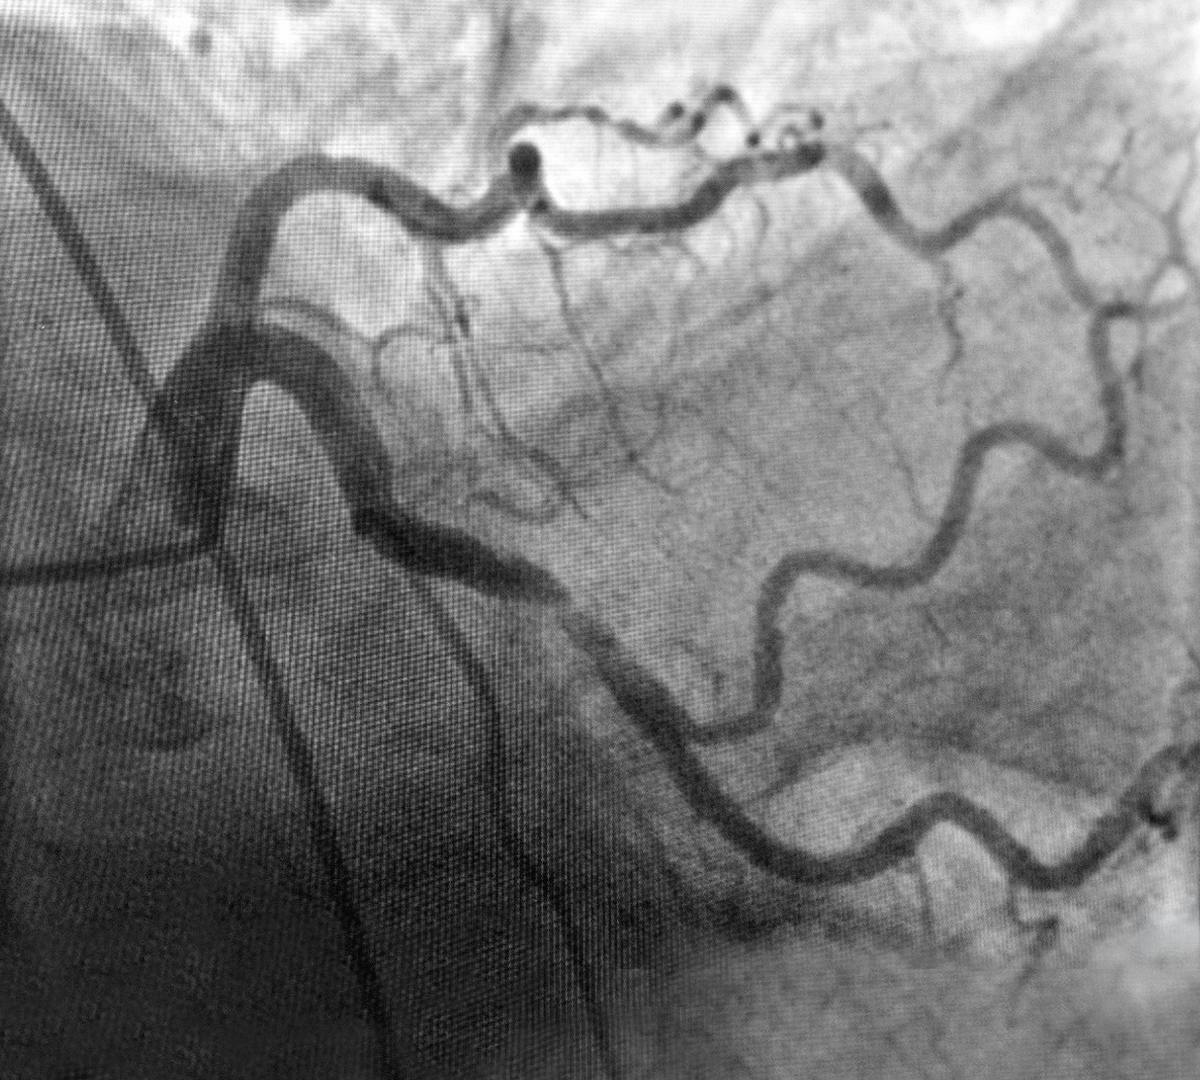

Ajunsă în sala de angiografie ARES Constanța, doctorul Nicolae Cârstea i-a efectuat angiografia coronariană, porcedură care evidențiează eventuale blocaje de la nivelul arterelor inimii.

În timpul procedurii, doctorul Cârstea a observat că pe una dintre arterele inimii ( ACX – artera circumflexă) există o îngustare, o stenoză de 80% responsabilă de durerea toracică resimțită de pacientă.

Tratamentul de elecție în astfel de cazuri este reprezentat de implantarea de stenturi, procedură denumită angioplastie coronariană. Practic, la nivelul vaselor îngustate, medicul cardiolog intervenționist implantează stenturi metalice pentru a reda circulația normală a sângelui și a salva mușchiul cardiac.

Astfel, în cazul prezentat mai sus, doctorul Nicolae Cârstea, medic cardiolog intervenționist la Ares Constanța, a efectuat angioplastia coronariană iar rezultatul este unul foarte bun.